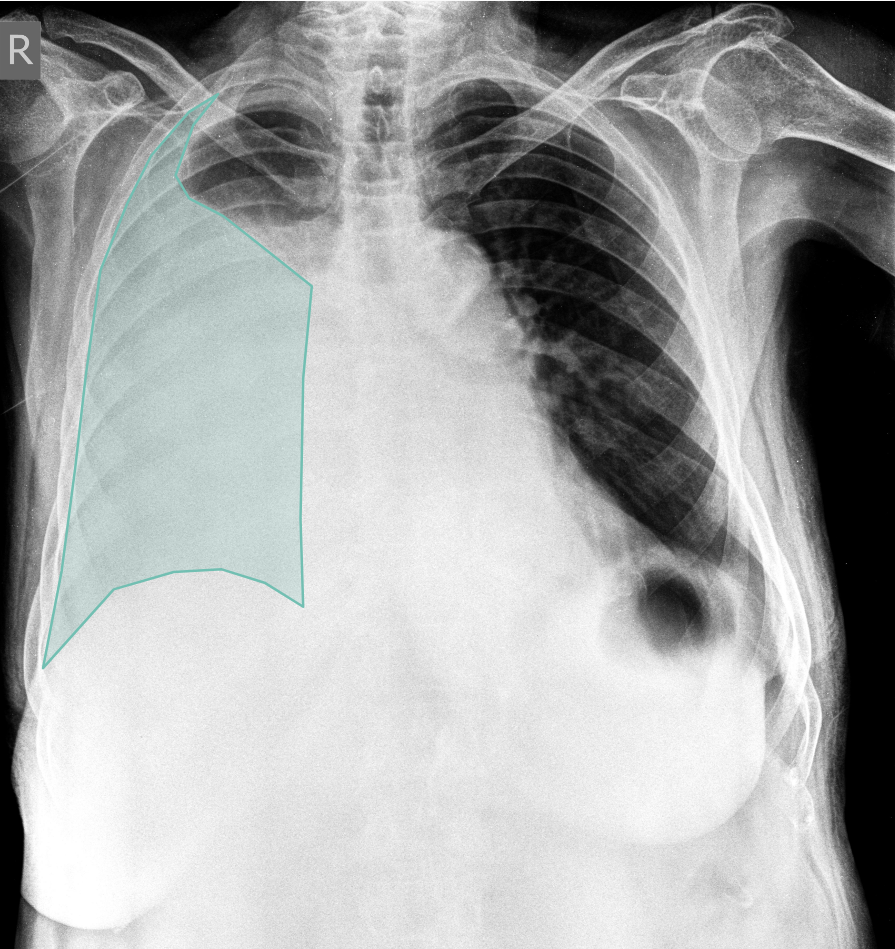

What does AI-detected pathology look like?

Eight examples of AI-annotated chest X-rays with color-coded pathology overlays

Chest X-ray with AI-detected Pleural Effusion highlighted

Pleural Effusion